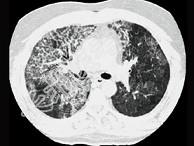

- 单项选择题24岁女性,咳嗽、进行性胸闷、气促2月, 支气管镜如图,镜下可见大量米汁样分泌物。影像学检查如图。可能的诊断是 ( )

A、肺泡蛋白沉积症